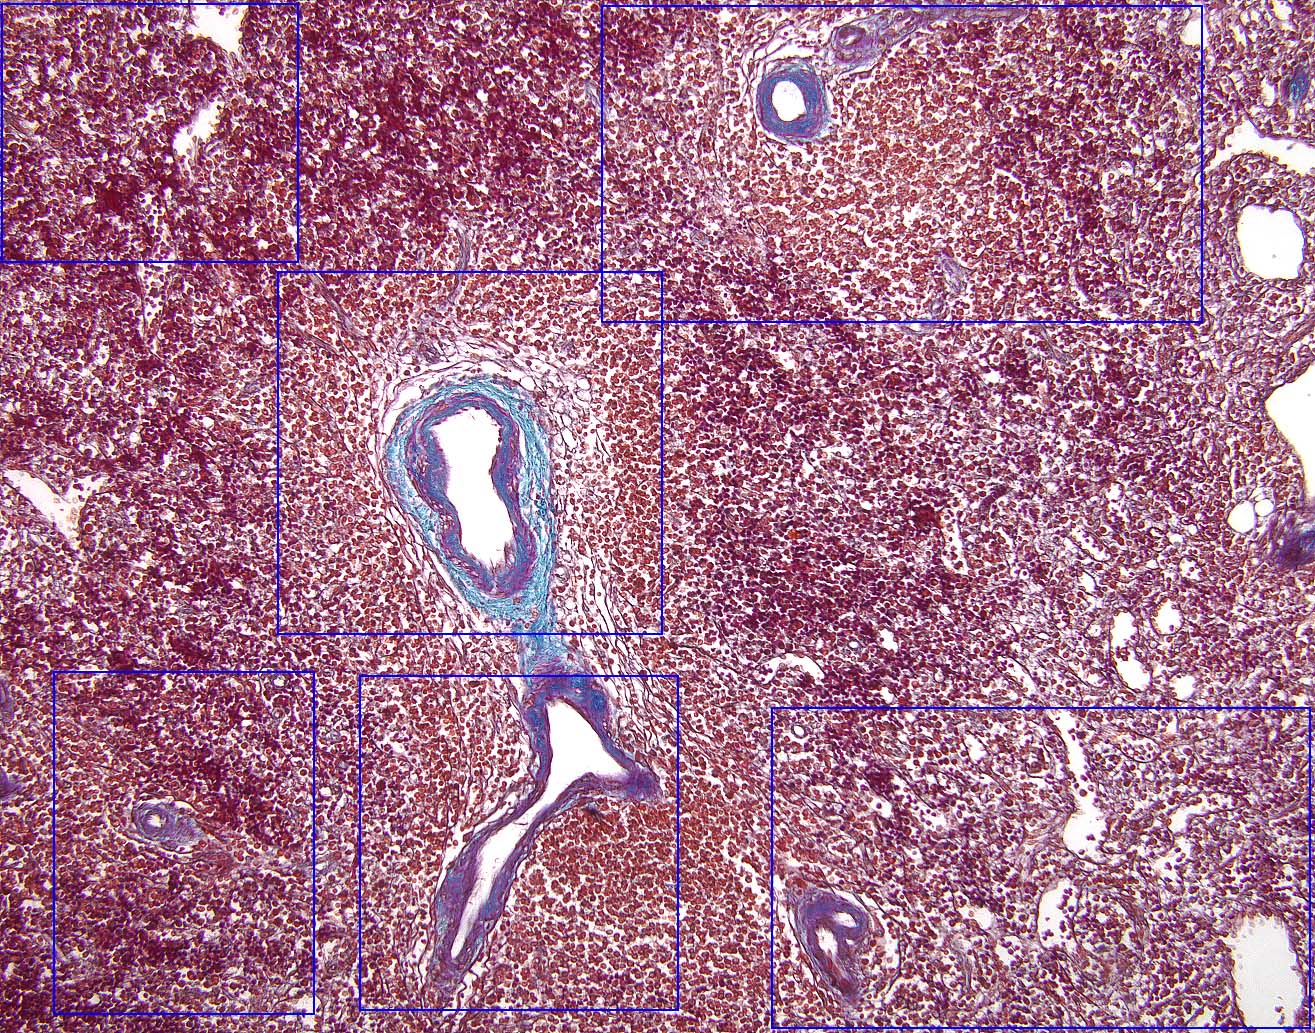

Return To Cartoon of Spleen